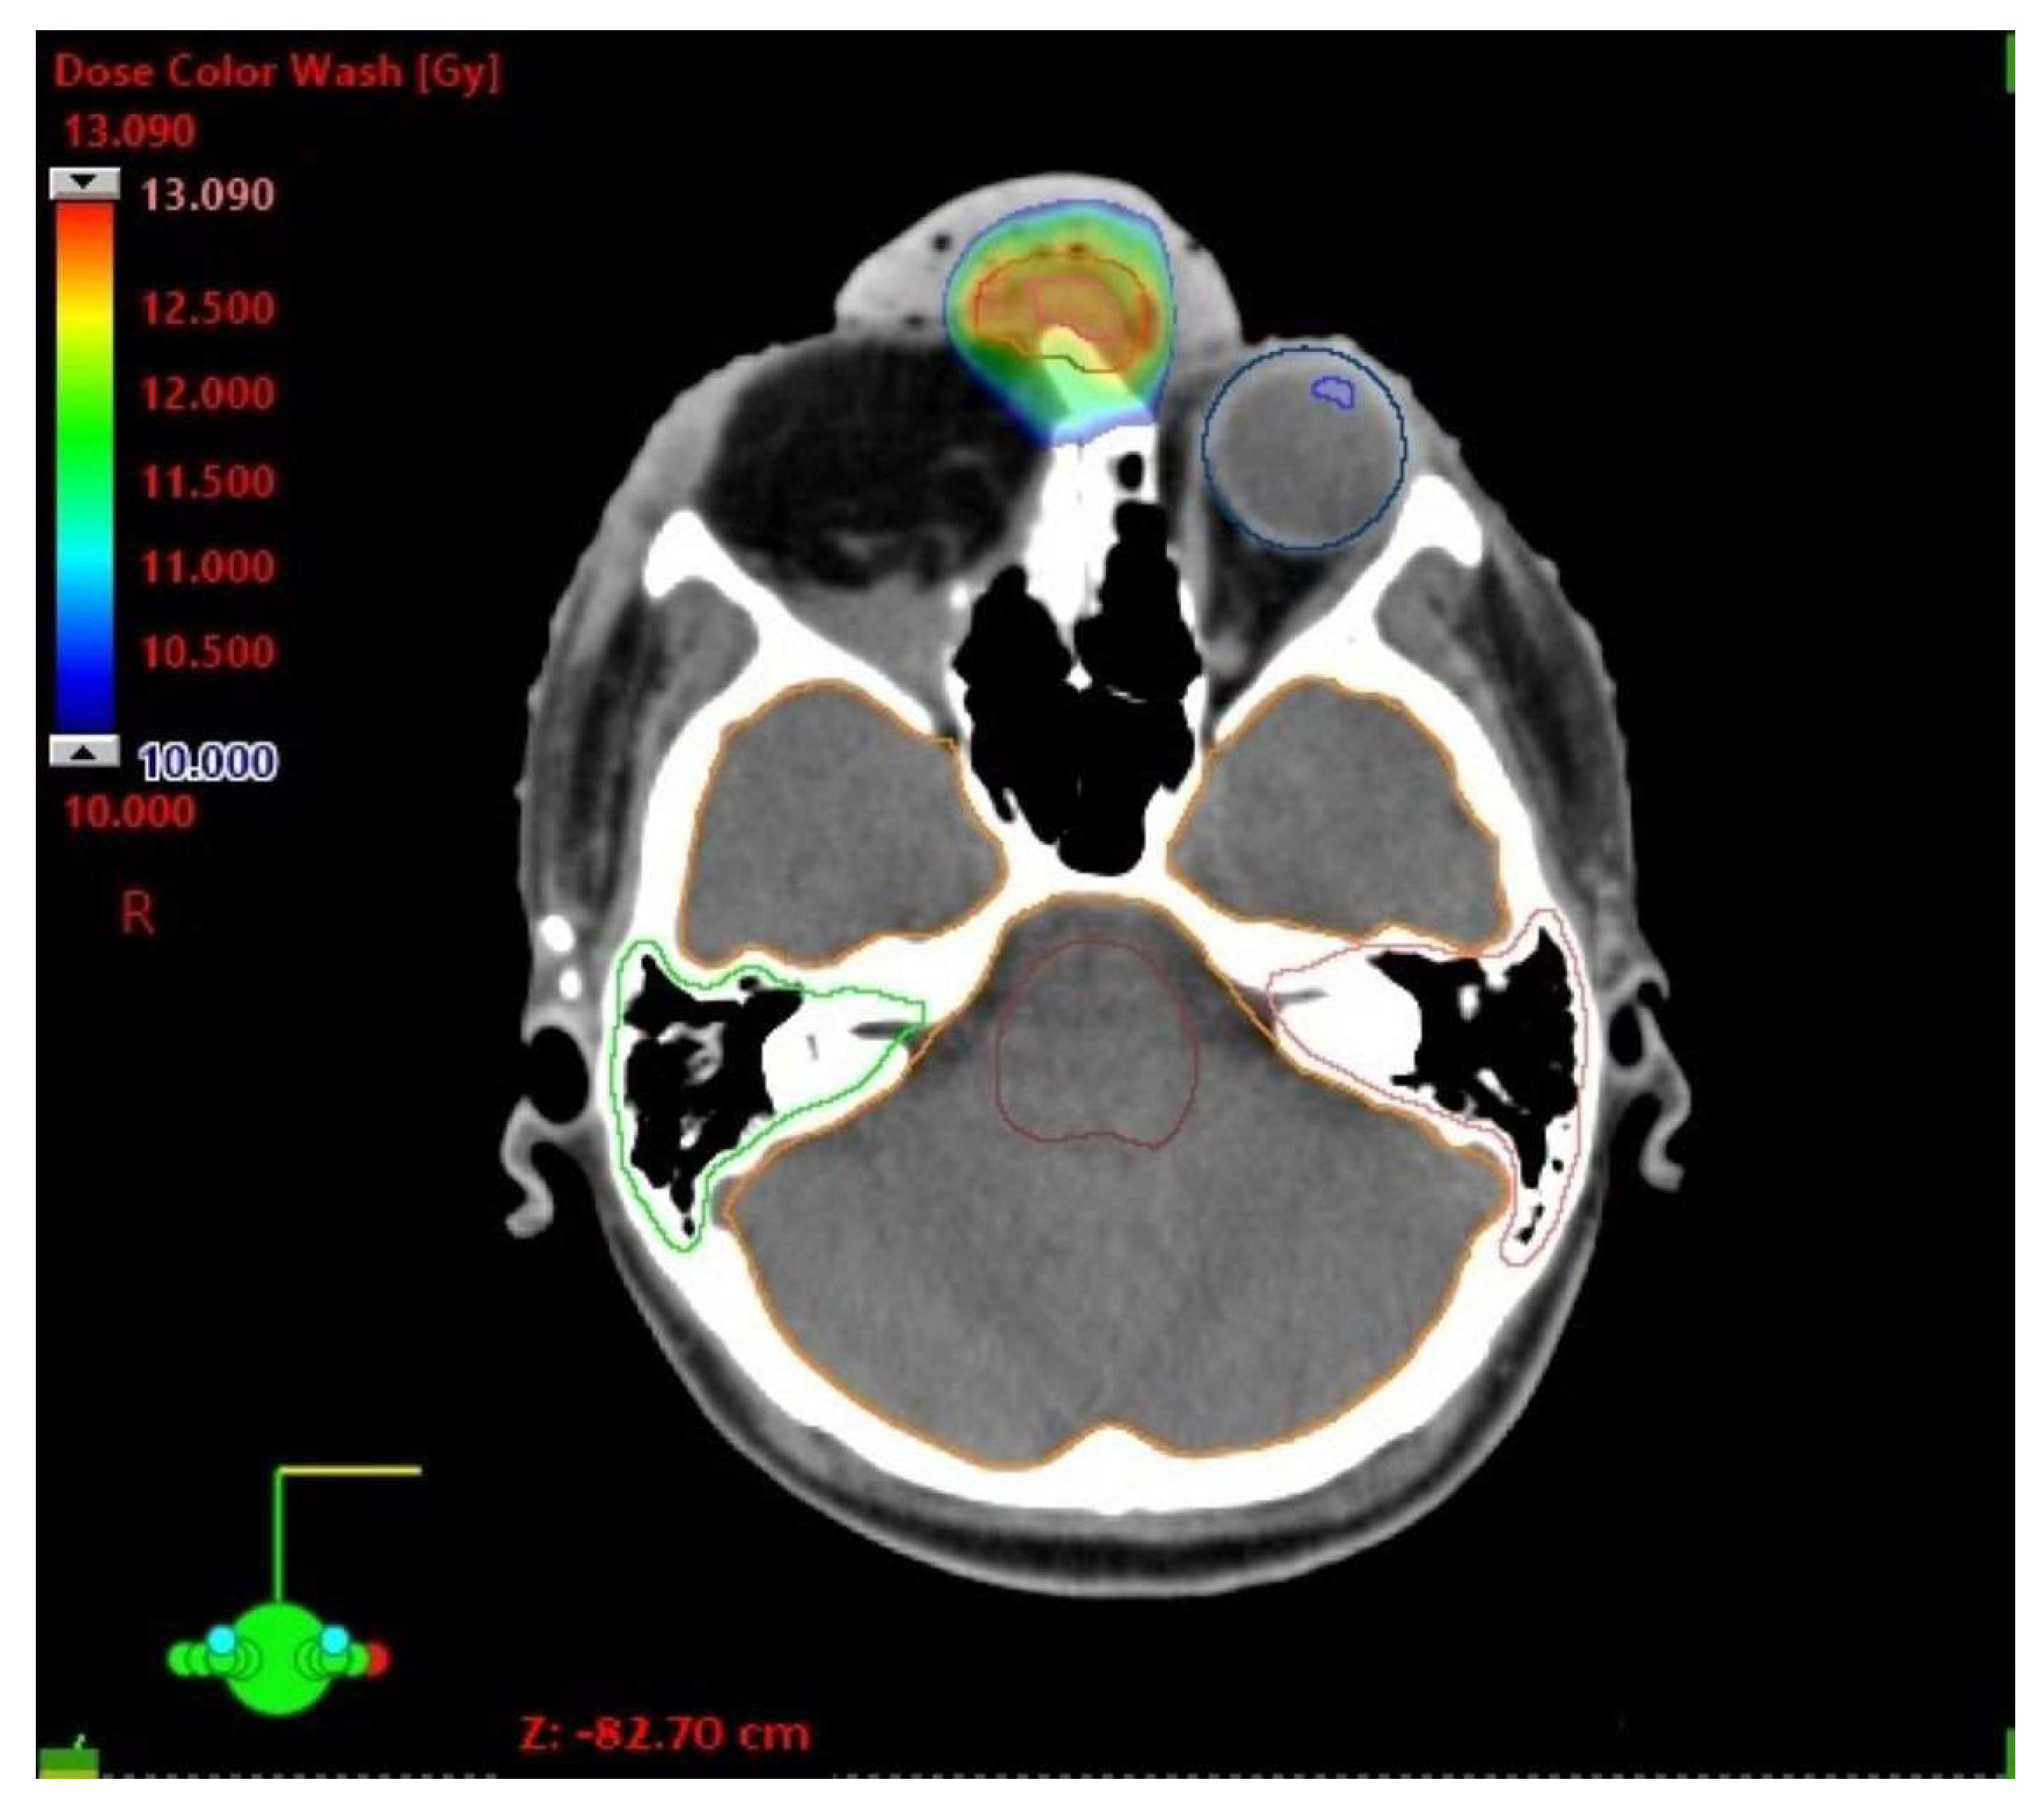

| D Max [Gy] | |

|---|---|

| Brainstem | 2.65 |

| Optic chiasm | 3.05 |

| Cochlea left | 0.95 |

| Cochlea right | 1.04 |

| Lens left | 0.22 |

| Eye left | 2.70 |

| Brain (ethmoid sinus region) | 9.00 |

| Optic nerve left | 2.26 |

| Spinal cord | 0.78 |